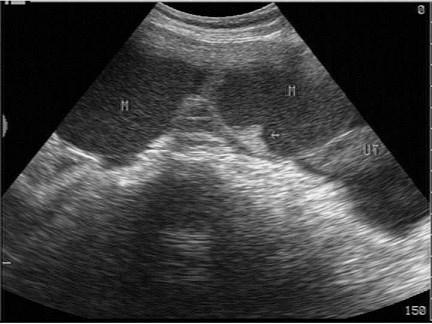

问题 女性,50岁,乏力、食欲下降、消瘦2月余。妇科检查盆腔触及包块。超声检查如图,最可能的诊断为?(?)

选项 A.输卵管积液 B.囊腺瘤 C.畸胎瘤 D.子宫肌瘤 E.转移性卵巢癌

答案 D